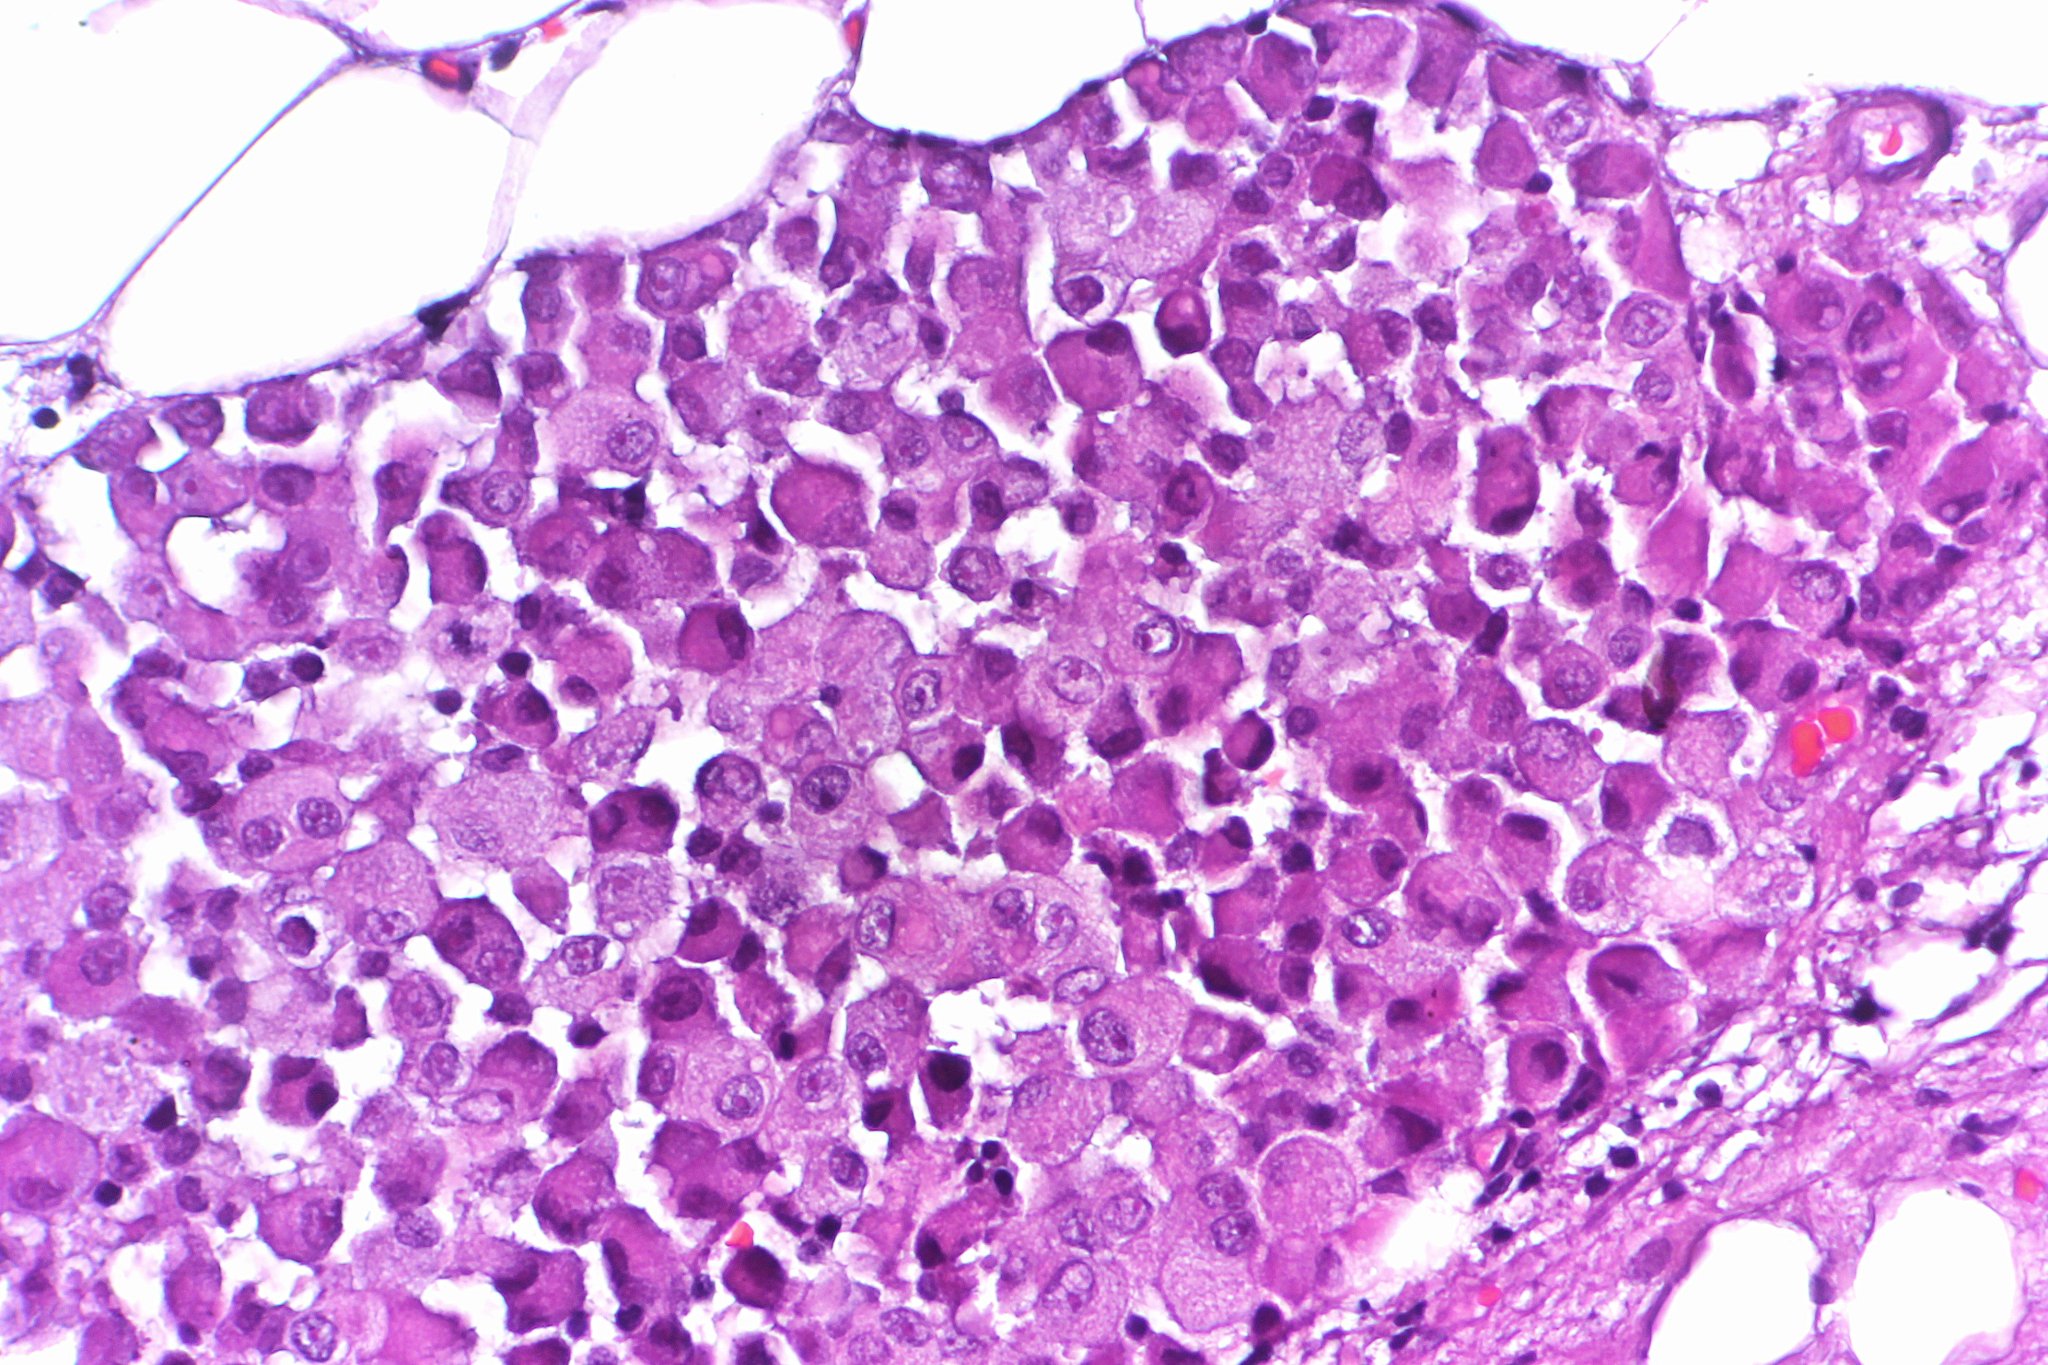

The epithelial cell type is identified by the clumping of cells and a square or cubic appearance. Sarcomatoid mesothelioma cells have a histological makeup that resembles sarcoma type cancers.

This process is part of mesothelioma pathology which involves examining either tissue or fluid to determine if this cancer exists in the body. Treatment and prognosis are affected by a patients. Histologically epithelial mesothelioma cells have polygonal ovoid or cuboidal cell shape.

Independently associated with worse overall survival proposed nuclear grading of epithelioid malignant pleural mesothelioma. Epithelioid mesothelioma is the most common mesothelioma cell type accounting for 50 to 70 of cases. However sarcomatoid mesothelioma like epithelioid mesothelioma is caused by genetically mutated mesothelial cells.

The occasional presence of signet ring cells may make it challenging to distinguish this disease from cancers of the lung. The three major mesothelioma cell types are epithelioid sarcomatoid and biphasic. Mesothelioma pathology focuses on understanding how mesothelial cells form spread and interact in the body.